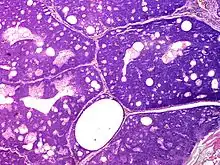

Sebaceoma (also known as a "sebaceous epithelioma") is a cutaneous condition that appears as a yellow or orange papule.[1]: 662